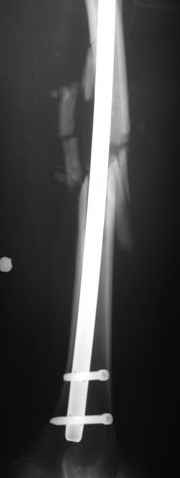

В приложении пример огнестрельного ранения бедра, оперированного на 2 сутки после ранения.

Штифтование было выполнено только на вторые сутки по причине задержки перевода из другого госпиталя, АБ профилактика была начата в другом учреждении, с момента госпитализации пациента к ним. Входное пулевое отверстие и зона введения штифта зажили первичным натяжением.

Единственно что наблюдал - замедленная консолидация, судя по серийным Рг граммам. В приведенном случае прии вялом мозолееобразовании сделал ошибку, решившись динамизировать гвоздь - перелом сросся со значительным укорочением бедра - повторная хирургия по удлинению бедра и проксимальным запиранием, больной мобилизован и вполне доволен(кстати заметить больной с ВИЧ инфекцией - изначально скомпрометированный иммунитет и несмотря на это, всё прошло без костной и мягкотканной инфекции.